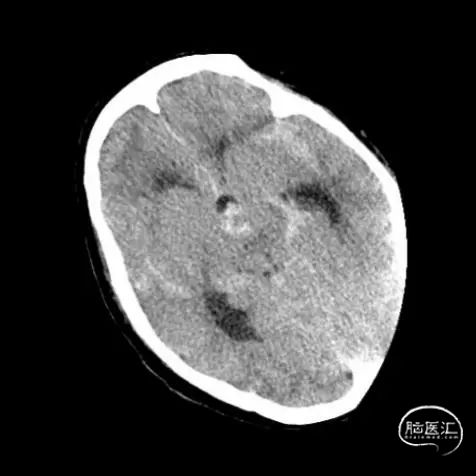

复查头颅CT提示广泛蛛网膜下腔出血,脑室扩张。基底动脉远端扩张请结合临床。急诊CTA提示:基底动脉两枚动脉瘤(图1)。